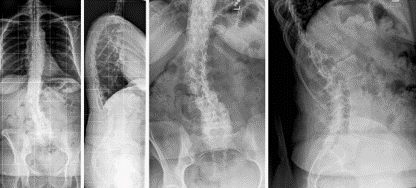

(2)上固定椎在交界区或存在交界性后凸

图6 长节段融合固定上固定椎(UIV)选择在胸10-12胸腰椎交界区是PJK的风险因素之一

(3)上固定椎位于T1-3

图7 术前-术后1个月-术后1个月外观